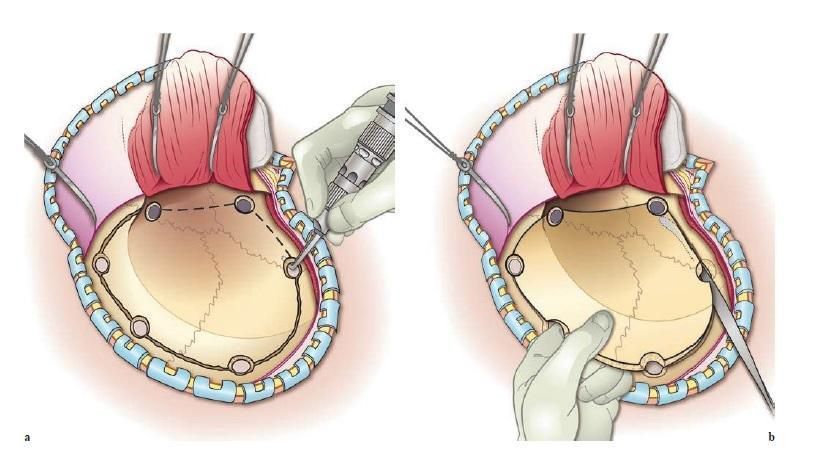

- Surgery in case of severe bleeding or swelling